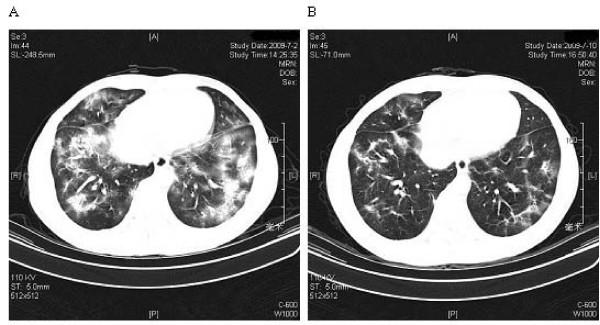

A 33-year-old male presented with a 1-month cough illness and fever lasting for 5 days. The chest radiograph revealed double lower lobe infiltrate, which was unresponsive to antibiotics. A cervical lymph node was first found in the development of this disease. Bronchoscopy, bronchoalveolar lavage and lung biopsy established the diagnosis of COP, while a lymph node biopsy was consistent with KFD. The patient improved on steroids.

病例介绍